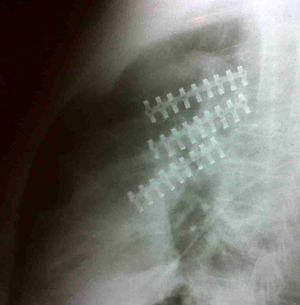

Casos clínicosCaso 1Paciente masculino de 61 años con antecedente de trauma cerrado de tórax al ser arrollado por un toro, trasladado al servicio de urgencias en donde entró en falla respiratoria por lo cual es intubado, requiriendo ventilación mecánica. En la valoración inicial se identificó gran deformidad de la pared torácica anterior izquierda con tórax inestable asociada a enfisema subcutáneo. En la radiografía de tórax se documentó neumotórax izquierdo, por lo que se realiza una toracostomía cerrada izquierda, y es trasladado a la unidad de cuidados intensivos; en este servicio se solicitó una tomografía axial computada de tórax que evidenció múltiples fracturas costales izquierdas desplazadas y neumotórax (fig. 1). Con estos hallazgos se pidió interconsulta a cirugía de tórax, quienes consideraron que el paciente era candidato para osteosíntesis de reja costal con placas de osteosíntesis de tercio de caña de 8 orificios con tornillos bicorticales, procedimiento que se realizó sin complicaciones con la utilización de sello de agua en el postoperatorio (fig. 2).